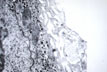

Reticulum

Fig 20 - RETICULUM:Stacks of collagen fibers in the Disse space.They stain black with silver impregnation.Is apparently produced by Ito cells.It forms the supporting framework of the hepatocytes.Its preservation in morbid conditions permits complete regeneration ad integrum while its destruction will produce scars,fibrosis and cirrhosis.